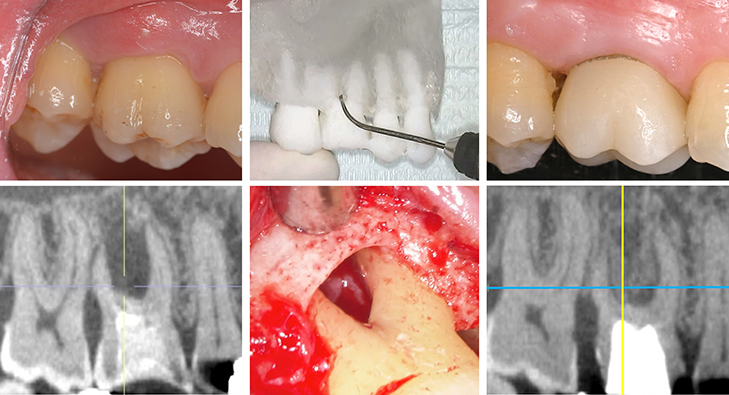

臨床研究では、成長因子や骨補填材などを用いた歯周組織再生療法を中心に、基礎研究の知見と連動した研究を遂行し、安全かつ科学的根拠に基づいた予知性の高い歯周病治療の確立を目標としています。

- 歯周組織再生療法に関する基礎および臨床研究

患者一人ひとりの病態やリスク因子を的確に評価し、歯周基本治療を軸とした上で、必要に応じて歯周組織再生療法や歯周形成手術を含めた歯周外科治療を実施しています。